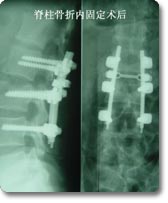

各种类型脊柱创伤的外科手术

脊柱外科是该科的主要临床特色, 也是该科近年来发展的重点。在七十年代初就在国内率先开展了颈椎前路手术,大大拓展了新桥医院骨科脊柱手术治疗的范围,在全国享有较高的知名度。随后又积极开展了脊柱脊髓损伤的临床治疗和基础实验研究, 目前已治疗患者1000余例,其优良的治疗效果和精谌的手术技巧深得同行好评,使脊柱骨折复位成功率和截瘫的恢复率得到显著改善和提高。